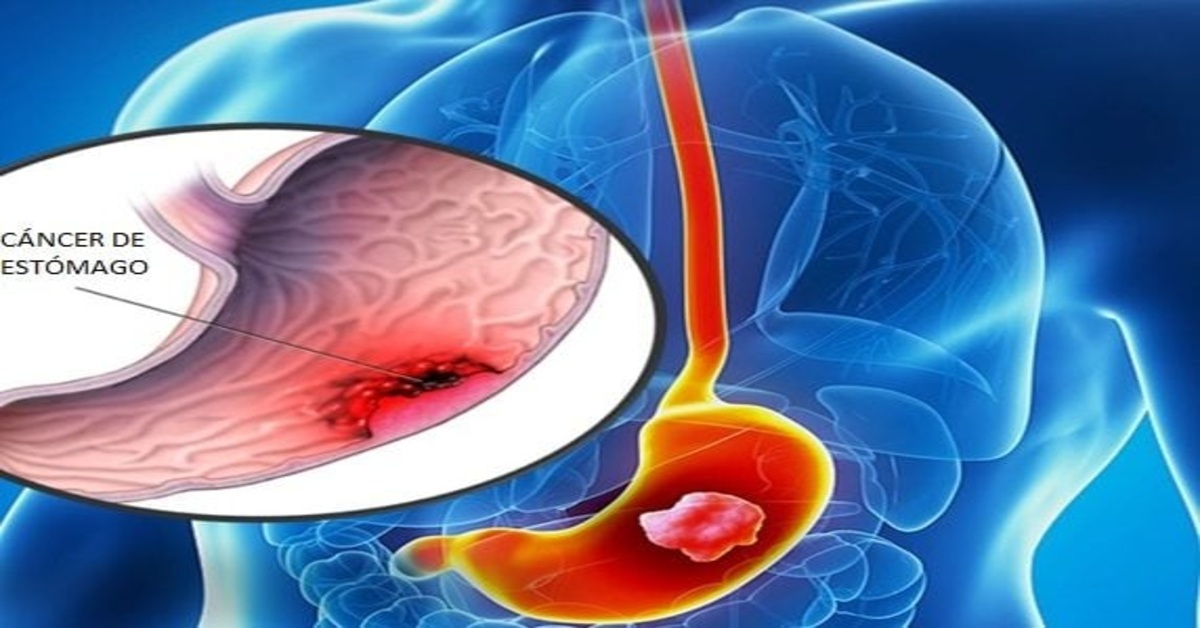

Muitas vezes, pequenos desconfortos digestivos são ignorados ou atribuídos a exageros na alimentação. No entanto, sintomas persistentes, como azia frequente, sensação de estômago cheio ou perda de apetite, podem indicar algo mais sério, incluindo o câncer de estômago. A doença é conhecida por seu crescimento silencioso, e muitos casos só são diagnosticados em estágios avançados, quando o tratamento se torna mais complexo.

O câncer de estômago é mais comum em homens e em pessoas acima dos 60 anos, mas não se restringe a esses grupos. A compreensão dos fatores de risco e dos sinais precoces pode ser crucial para um diagnóstico oportuno e aumento das chances de sucesso no tratamento.

Diagnóstico Precoce

O primeiro passo diante de sintomas suspeitos é a consulta médica. Além da avaliação clínica, a endoscopia é um exame essencial, permitindo visualizar o interior do estômago e colher biópsias de áreas suspeitas. Exames complementares, como tomografia e ressonância, ajudam a determinar o estágio do tumor e verificar a presença de metástases. Quanto mais cedo for realizado o diagnóstico, maiores são as chances de tratamento bem-sucedido.